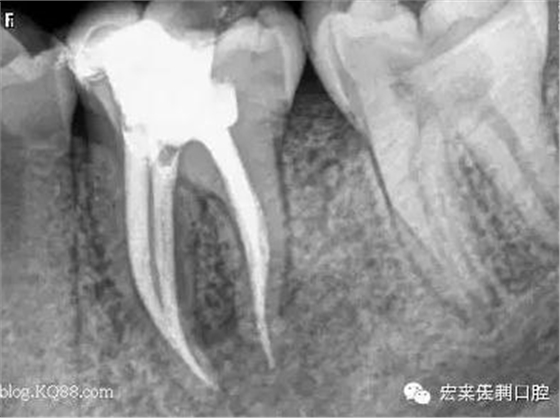

例如,我們有位女患者,在我們門診部根管治療結(jié)束后,建議她做個牙冠保護(hù)起來,她當(dāng)時沒有聽取意見,過了三個月左右牙已劈裂。沒有任何辦法補(bǔ)救了,只能選擇拔掉一半,之前做的根管治療也前功盡棄。如圖: